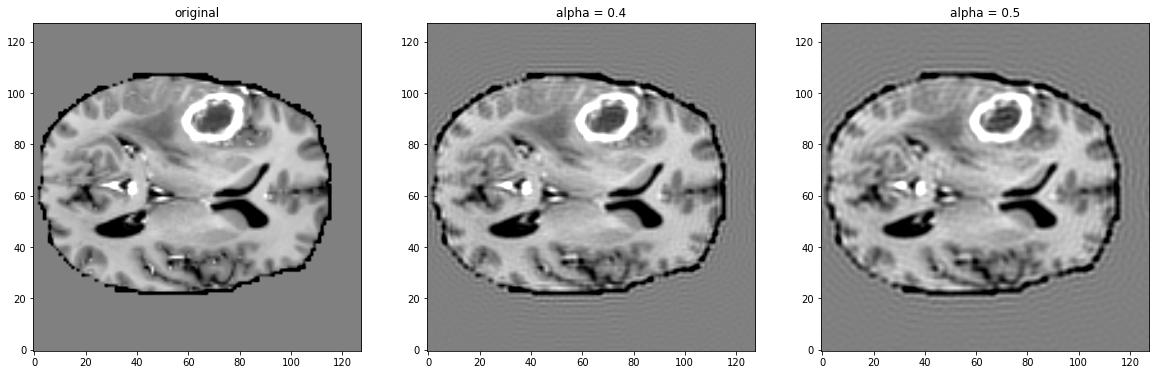

Hi @rijobro, here one can see the transform applied on a sample image from the BraTS dataset. Leftmost is the original volume, then separate applications of the transform with different strengths. |